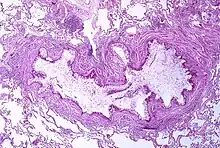

Pathophysiology

Asthma is the result of chronic inflammation of the conducting zone of the airways (most especially the bronchi and bronchioles), which subsequently results in increased contractability of the surrounding smooth muscles.[21] This among other factors leads to bouts of narrowing of the airway and the classic symptoms of wheezing. The narrowing is typically reversible with or without treatment. Occasionally the airways themselves change.[21] Typical changes in the airways include an increase in eosinophils and thickening of the lamina reticularis.[20] Chronically, the airways' smooth muscle may increase in size along with an increase in the numbers of mucous glands.[20] Other cell types involved include T lymphocytes, macrophages, and neutrophils. There may also be involvement of other components of the immune system, including cytokines, chemokines, histamine, and leukotrienes among others.[20]